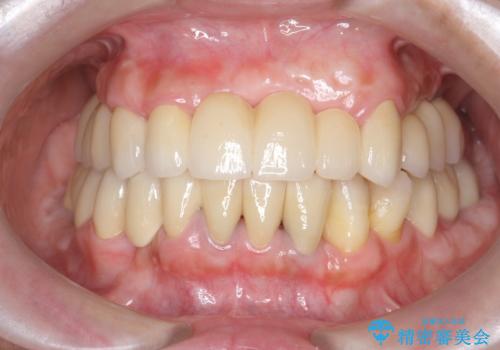

[20代男性] インプラント 失った歯の治療

![[20代男性] インプラント 失った歯の治療の症例 治療後](https://seimitsushinbi.jp/wp/wp-content/uploads/2019/11/IMG_9922-1-500x350.jpg?v=1574736466)